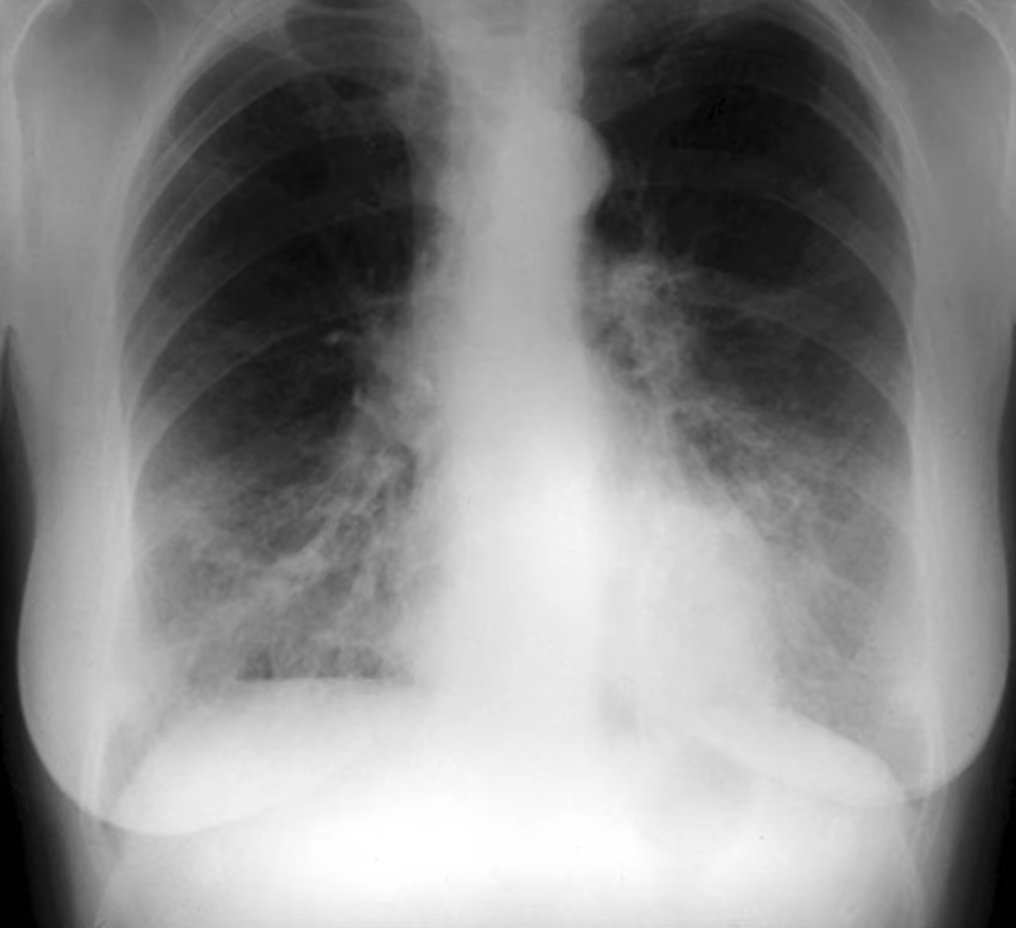

Atelactasis

- Loss of lung volume due to collapse

- Lobar atelactasis usually occurs from airway obstruction

- Findings seen in all anatomic variations of lobar collapse are:

- Elevation of the ipsilateral hemidiaphragm

- Mediastinal shift towards the side of collapse

- Juxtaphrenic peak sign (particularly with upper lobe collapse)